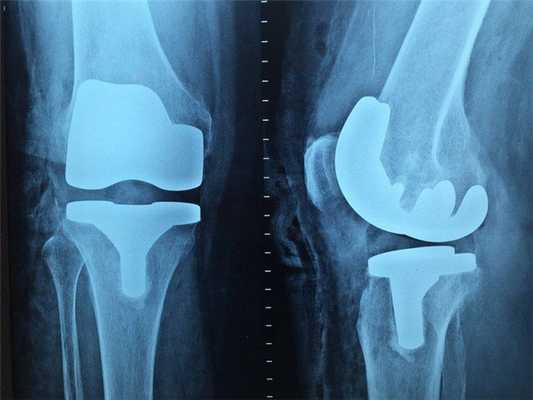

Рентген

Наиболее старый и привычный метод визуализации человеческого тела. Применяют рентген повсеместно, от хирургии до стоматологии. Метод прост и понятен: человека облучают особыми лучами, которые легко проходят сквозь мягкие ткани и задерживаются в твёрдых. Благодаря этому принципу, на фотоплёнку или датчик, расположенные на противоположной от источника лучей стороне, передаётся изображение, а в распоряжение врача попадает рентгенография или рентгеноскопия.

Главные плюсы такого обследования: быстрота и стоимость. Рентгеновскими аппаратами оснащены практически все больницы, процедура проходит быстро и стоит недорого.

Главные минусы: облучение и качество изображения. При проведении рентгенографии пациент облучается, а картинка получается двумерной. Врач с трудом может разглядеть внутренние органы по отдельности, поскольку их тени перекрывают друг друга. Также невозможно детально разглядеть хрящевую ткань и мозг. Хрящи практически не задерживает лучи, мозг надёжно закрыт черепной коробкой. Для их исследования рентгенография не подойдёт.

Наиболее эффективно будет проводить рентгенографию при повреждениях костей, суставов и зубов.

В каких случаях лучше делать рентген?

Классический рентген по-прежнему остаётся важным методом для диагностики самых разных заболеваний. Например, маммография (рентгеновское исследование молочных желез) - лучший способ скрининга рака молочной железы. Возможности КТ в выявлении злокачественных и воспалительных процессов в этом органе существенно ниже.

Доза радиологического облучения при КТ значительно выше, чем при рентгеновском исследовании, не стоит «бить из пушки по воробьям». К примеру, при подозрении на перелом или при первичном обращении с болью в суставах предпочтительнее сделать рентген.

Что покажет рентген

Рентген - это самый широко доступный тип обследования. В Санкт-Петербурге его можно сделать быстро на платной или бесплатной основе как в частных, так и в государственных клиниках и больницах. Основная задача рентгенографии - дать общее представление об изменении структуры органов и костной ткани. С помощью рентген-аппарата врач может хорошо визуализировать:

- инородные тела;

- переломы;

- воспаление легких;

- рак молочной железы;

- туберкулез.

Основное преимущество рентгенографии заключается в том, что это быстрый и дешевый метод сканирования. Однако по точности и диагностической ценности он безусловно уступает как УЗИ, так и таким высокотехнологичным методам исследования, как МРТ и КТ.

В основе физики работы рентген-аппарата лежат просвечивающие способности рентгеновских лучей. Получение плоского двухмерного изображения основано на ослаблении рентгеновского излучения при его прохождении через различные ткани. При рентген-сканировании пучок излучения, проходя через ткани организма, которые обладают различной плотностью, рассеивается и тормозится. Таким образом, на пленке возникают изображения разной степени интенсивности. Лучевая нагрузка при рентгенографии небольшая, но она всегда есть и может составлять от 0,1 до 1 мЗв. Поэтому рентгенография запрещена для беременных женщин, а здоровому человеку рентген можно делать 1- 2 раза в год.

Кроме дозы облучения у рентгеновского сканирования есть один существенный диагностический недостаток - плоская картинка. Поскольку рентген изображения - это тень ткани на пленке, объемно оценить органы и структуры человеческого тела с помощью рентгена не получается.